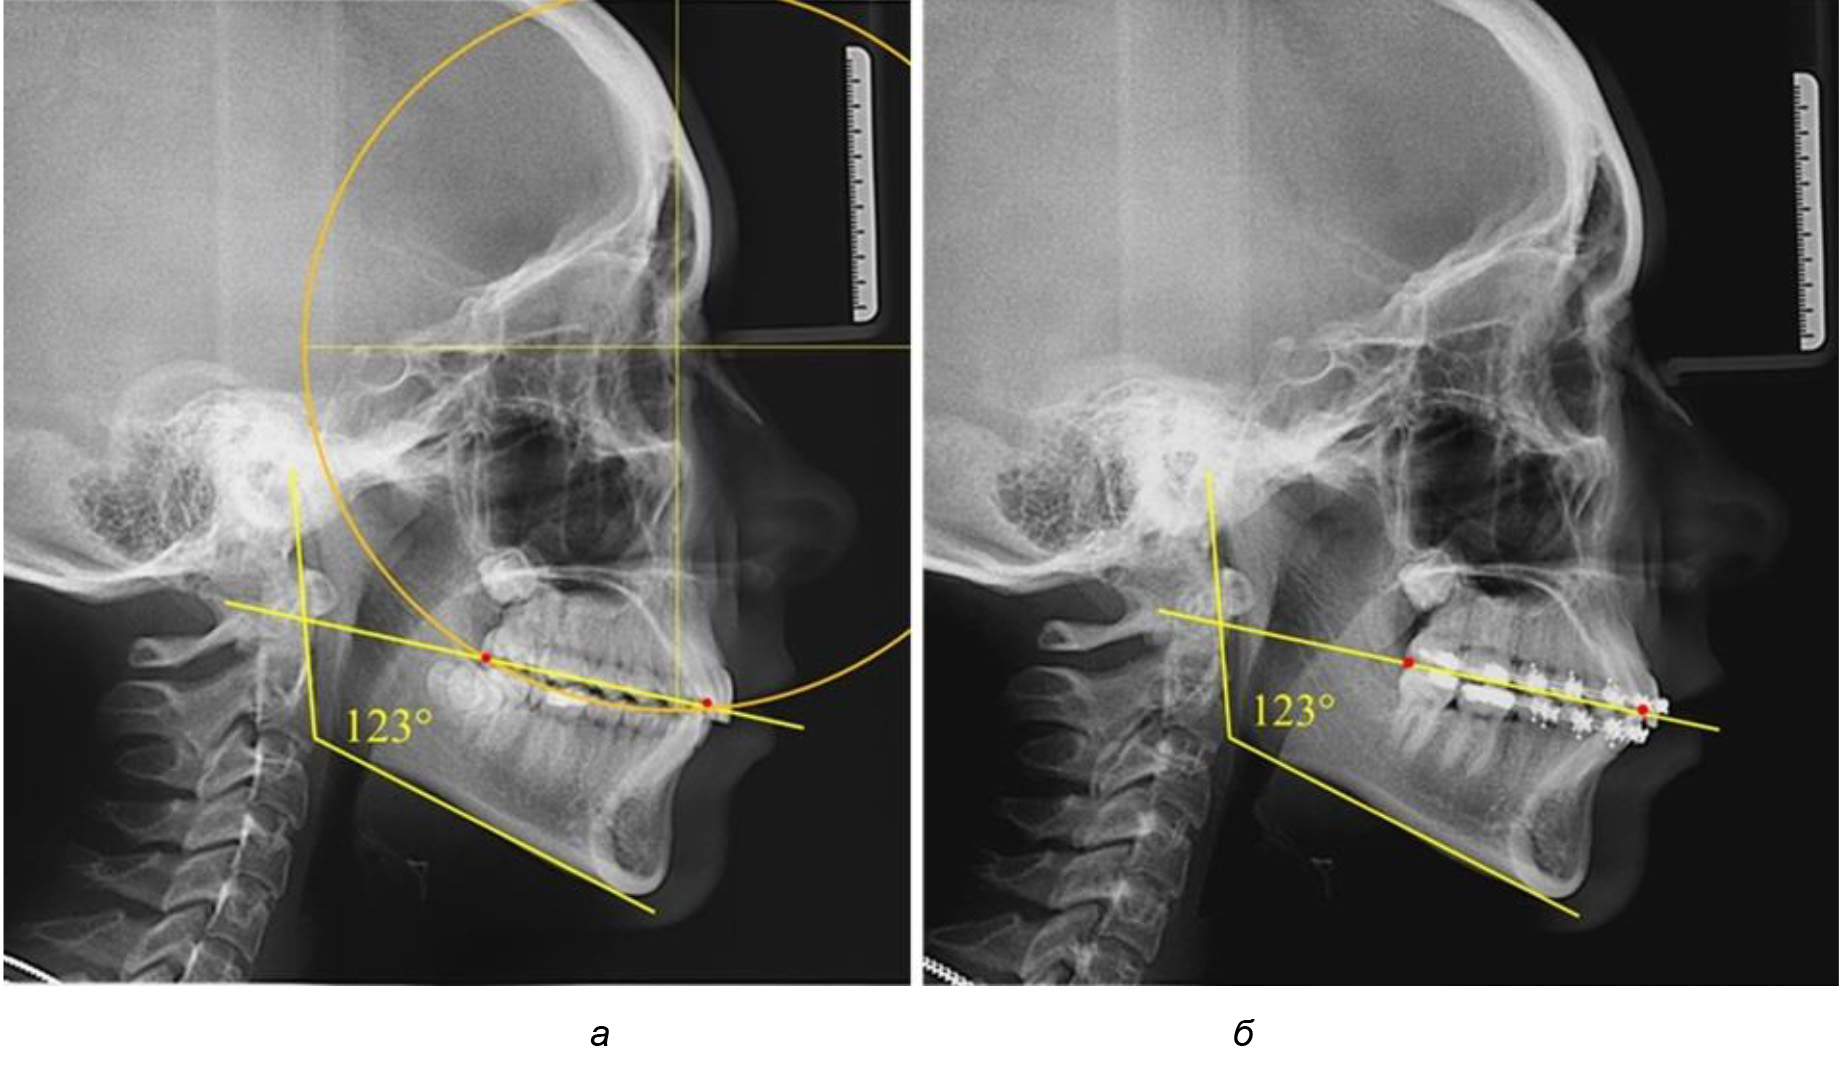

Таким образом, проведенное лечение техникой «прямой» дуги способствует нормализации окклюзионного равновесия и торку передних зубов, однако не соответствует оптимальному окклюзионному статусу, характеризующему физиологическую окклюзию. При этом величина нижнечелюстного угла оставалась на прежнем уровне (рис. 5).

Рис. 5. Особенности ТРГ при патологической кривой Spee до лечения (а) и после лечения (б) техникой «прямой» дуги